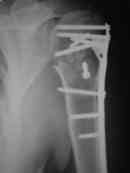

закрытый оскольчатый перелом проксимального отдела левой плечевой кости со смещением отломков (b1_xr.jpg). 06.04.2007 оперирована в одном из отделений: открытая репозиция, накостный остеосинтез проксимального отдела левой плечевой кости. Выписана с заключительным диагнозом: а)основной: закрытый 4-х фрагментарный (по Ниру) перелом проксимального отдела левой плечевой кости, со смещением отломков; б) осложнения основного: нейропатия левого локтевого нерва; в) сопутствующий: миокардитический миокардиосклероз ХСН 0-1.

В момент осмотра: нормостеническая конституция, по передней поверхности плечевого сустава – рубец. Рука в положении приведения. Отведение не более 10 град, дальнейшие движения с лопаткой до 20-25 град. Амплитуда сгибания-разгибания 10-15 град. Ротация отсутствует. Пальпаторно - выраженная болезненность над суставом, особенно в проекции клювовидного отростка. При попытках пассивных движений – боль. Рентгенограммы и результаты КТ приложены(b2(3)_xr.jpg, b1(6)_ct.jpg).

Диагноз: неправильно сросшийся в условиях накостного остеосинтеза оскольчатый перелом головки левой плечевой кости (11-С3.2), асептический некроз головки плечевой кости, смешанная артро-миогенная контрактура левого плечевого сустава; демиелинизирующая нейропатия левого локтевого нерва.